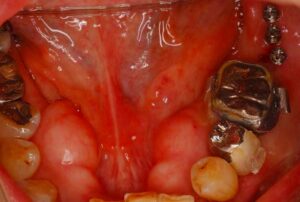

• 症例2014-013

ショートインプラント症例

今日のインプラントの症例は、ちょっと面白い症例です。 左の上の歯が3本なくて、しかも骨の高さが足りませんでした。そこで、造骨する事無く後ろ側に二本のショートインプラントをいれました。 そんな、症例のCT画像です。 インプラントにもただ、白い […] 本文を読む